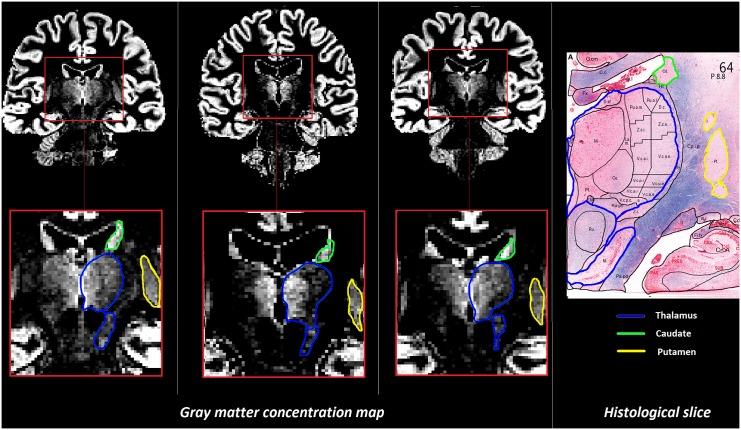

The existence of partial volume effects in brain MR images makes it challenging to understand physio-pathological alterations underlying signal changes due to pathology across groups of healthy subjects and patients. In this study, we implement a new approach to disentangle gray and white matter alterations in the thalamus and the basal ganglia. The proposed method was applied to a cohort of early multiple sclerosis (MS) patients and healthy subjects to evaluate tissue-specific alterations related to diffuse inflammatory or neurodegenerative processes.

Forty-three relapsing-remitting MS patients and nineteen healthy controls underwent 3T MRI including: (i) fluid-attenuated inversion recovery, double inversion recovery, magnetization-prepared gradient echo for lesion count, and (ii) T1 relaxometry. We applied a partial volume estimation algorithm to T1 relaxometry maps to gray and white matter local concentrations as well as T1 values characteristic of gray and white matter in the thalamus and the basal ganglia. Statistical tests were performed to compare groups in terms of both global T1 values, tissue characteristic T1 values, and tissue concentrations.

Significant increases in global T1 values were observed in the thalamus (p = 0.038) and the putamen (p = 0.026) in RRMS patients compared to HC. In the Thalamus, the T1 increase was associated with a significant increase in gray matter characteristic T1 (p = 0.0016) with no significant effect in white matter.